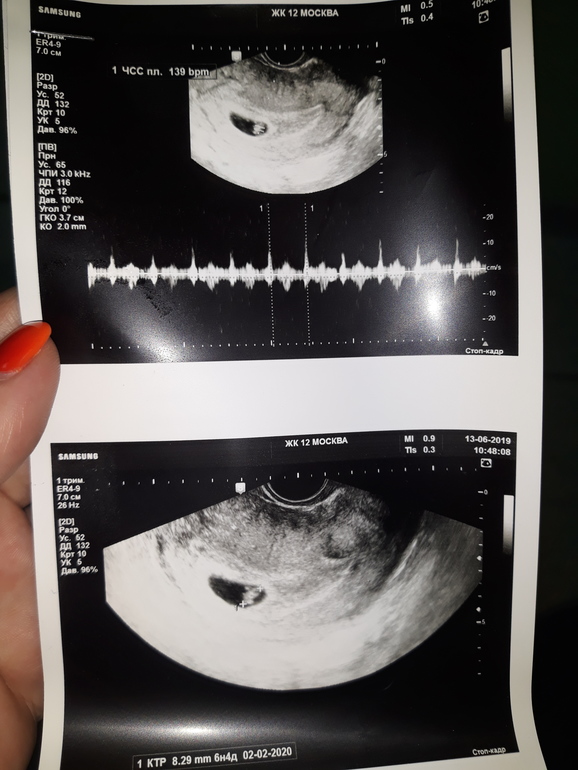

Страхи, переживания и немножечко нытьяНачиталась я про ЗБ и мне стало очень страшно... 13.06 была на узи, сердечко бъется, но из-за тонуса деформировано ПЯ... Диагноз: угроза прерывания...

Болит живот, тянет очень сильно, и поясницу тоже. Гиня хотела направить в стационар, я написала отказ, так как с детьми сидеть некому, а младшему всего 1,5 года... Прописала дюфастон, магне и свечи папаверин 2 раза в день. Сегодня вообще начались какие то боли другие внизу живота, режущие, выделения чистые, белые, тонус так и продолжается, очень сильно его чувствую периодически. Грудь стала мягкая, токсикоз прошёл вроде... Короче читаю весь день про ЗБ и к вечеру уже все симптомы ее собрала на себе, кроме кровотечения или выделений с кровью... Но их же может и не быть??? К гине на приём только 27 июня, я с ума сойду за 10 дней. Стараюсь больше лежать. Может я себе накручиваю? Но я так боюсь... Я ВБ еле пережила, а если еще и ЗБ будет, то меня вообще кондратий хватит...